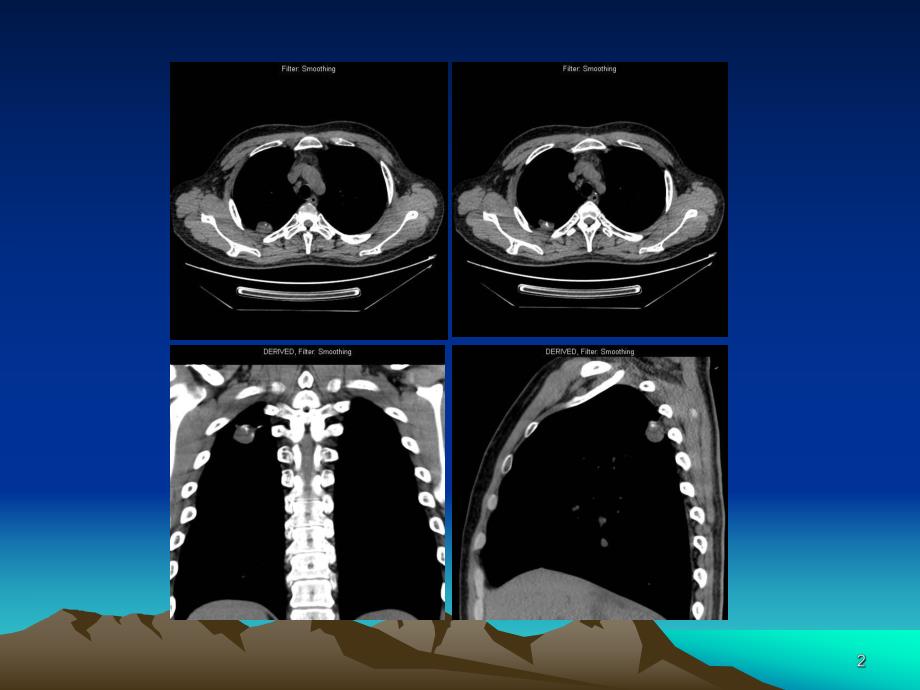

1、 患者:孙X 男 25岁 查体发现 患者:温玉珍 女 81岁 查体发现 肺错构瘤是指包含肺的所有正常组织成分,但构成成分数量异常、排列异常或分化程度异常等所形成的肿瘤样畸形 目前是最常见的肺部良性肿瘤,占肺部良性肿瘤的75%,孤立性肺结节的8%多发生于中年人,平均年龄为4050 岁,男性多于女性 有人提出胚胎发育过程中,将要发育成支气管的一部分组织,因某些原因发生脱落、倒转等发育异常,被正常的肺组织包裹,逐渐发展成瘤样结构 病理组织学特点病理组织学特点 镜下表现为由分化成熟结构紊乱的组织成分组成的瘤样增生,由血管、纤维组织、脂肪、平滑肌、神经及软骨成分等组织构成 发生于肺段以上支气管者称中央型

2、,发生于肺段以下者称周围型病理所见病理所见 瘤组织内可见透明软骨细胞和瘤组织内可见透明软骨细胞和脂肪细胞脂肪细胞病理所见病理所见 瘤组织内可见大量成熟的透明瘤组织内可见大量成熟的透明软骨细胞软骨细胞 临床症状和发生部位有关 中央型者可有咳嗽、发热、肺部阻塞性感染 周围型者常无症状,多为体检时发现 X线表现线表现 中央型者可为叶、段的肺部炎症表现或肺不张。周围型者见肺内单发性球形病灶,直径约2-3cm 者多见,边缘清楚、光滑,较大者边缘可呈波浪状。纤维型者密度较均匀,软骨型者瘤内可见有特征性爆米花样钙化。右肺错构瘤,边缘光滑锐利,无明显 分叶。病例同前,侧位胸片显示同正位。CT表现表现 病灶边缘

3、光滑,多呈圆形或类圆形,无毛刺征,可有分叶征,可见血管影进入病灶内,多由分叶处进入,多为单发。病灶直径多小于5cm。肿块多为软组织密度肿块,其内多有脂肪密度区,为其典型CT表现。CTCT表现表现 病灶内钙化为斑点状或斑片状,典型钙化为爆玉米花样。肿块多位于肺内,少数可靠近肺门,亦可位于气管腔内,肺门及纵隔内无肿大淋巴结。增强后肿块无强化或仅轻度强化。含脂肪成分含脂肪成分 含钙化成分含钙化成分左肺上叶错构瘤(中央型)左肺上叶错构瘤(中央型)病例同前病例同前 瘤组织内可见点状钙化影(上方箭瘤组织内可见点状钙化影(上方箭头)和脂肪成分(下方箭头)头)和脂肪成分(下方箭头)MRI表现表现 T1W I一